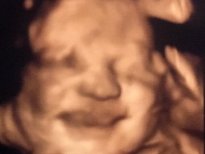

Anne adayları için en heyecanlı an olan bebeğin anne karnında ilk görüntüleri, görenlere 'Adeta poz vermiş' dedirtiyor. 16'ncı haftadan itibaren yüzü şekillenmeye ve gelişmeye başlayan bebeklerin ultrasonla çekilen fotoğrafları arasında kaşları çatık, gülen, eliyle yüzünü kapatan, burnuyla oynayan, parmağını emen, elini çenesine dayayan bebekler olduğu gibi kendini göstermeyen bebekler de var.